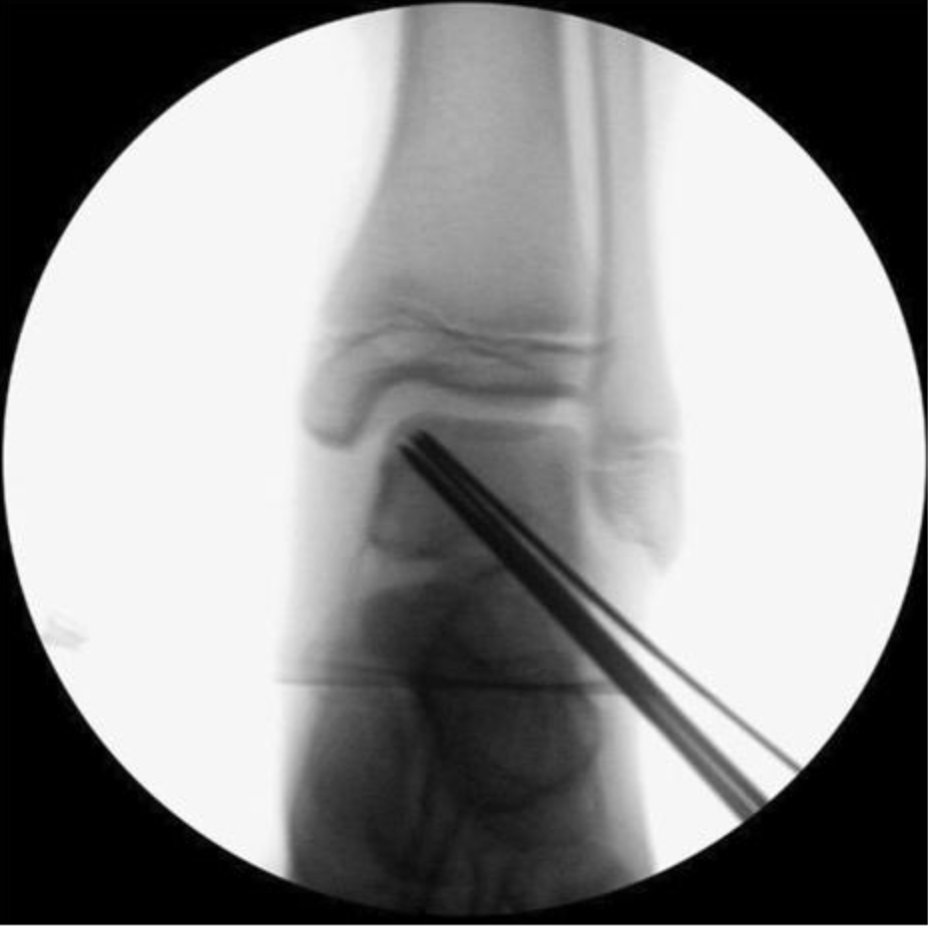

逆行钻孔逆行钻孔可通过X线透视或计算机辅助设备结合专用导向器械进行,使用 1.1-2.4mm 不同直径克氏针。原则上选择针径时需确保可多次钻孔,且克氏针足够稳固不折断。